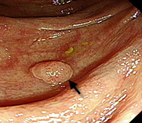

既然是基因突變而來,其轉變需要時間,因此大部分的大腸癌發生之前只是大腸息肉,這個階段算是良性腫瘤,雖然偶爾會出血,但通常沒有任何症狀(圖一)。若未發現也未切除,息肉就可能會逐漸演變為大腸癌。大腸癌的症狀隨生長位置不同而有所不同。直腸或乙狀結腸的腫瘤出血會造成明顯的血便,但較深處的腫瘤出血會與糞便充分混合後再排出體外,因此患者不見得會發現。直腸的腫瘤較靠近肛門,因此患者總是會感到想排便,但即使排便後還是有排不乾淨的感覺。直腸或乙狀結腸的腫瘤會造成腸管狹窄,所以糞便變得較細。相對來說盲腸或深處結腸的腫瘤不會改變糞便形狀,但可能直接造成阻塞,出現腹脹、嘔吐的情形。有時腫瘤太大,可能破壞其鄰近的器官,例如膀胱、陰道、子宮等等,而產生各器官相關的症狀。大腸癌較末期時,會因為長期出血而導致貧血症狀,而且轉移性腫瘤可能會有腹脹、黃疸、咳嗽、骨頭痛等情形。這時通常會合併疲倦、食慾差、消瘦等現象。

圖一 大腸鏡發現一顆小息肉(箭頭所指),為良性息肉,發現後已當場切除,排除了將來逐漸演變成大腸癌的危險。